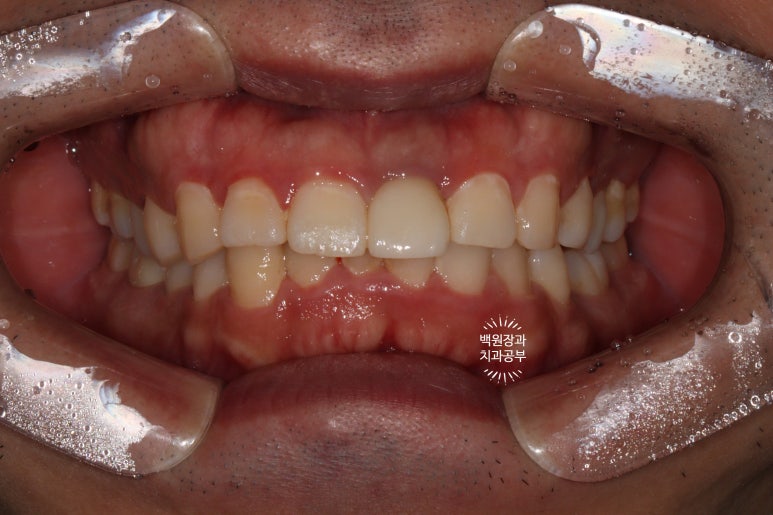

생각보다 자연스러운 색의 치아와 (white esthetic) 잇몸의 색깔을 보실 수 있습니다. (pink esthetic)

옆에서 보면 왠지 치아 주변이 조금 검은듯한 느낌이 들기는 하나,

바로 옆에 위치한 또다른 가운제 앞니와 비교했을 때 큰 차이 없이 적절한 외형의 임플란트 보철물을 보실 수 있어요.

앞에서 볼 땐 꽤나 자연스러운데,